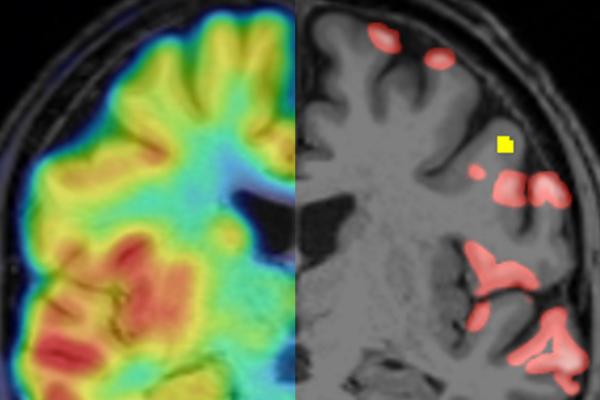

Using PET-imaging to detect cortical synapse loss in multiple sclerosis

A team around Martin Kerschensteiner has demonstrated for the first time that positron emission tomography (PET) can be used to visualise synapse loss in MS lesions in the cerebral cortex.